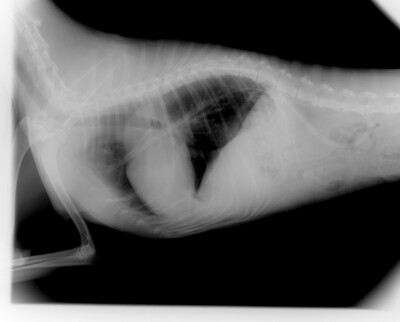

レントゲン検査

中心部にある楕円状の塊が心臓で、その斜め上に肺腫瘍を疑う丸い塊を認めています。